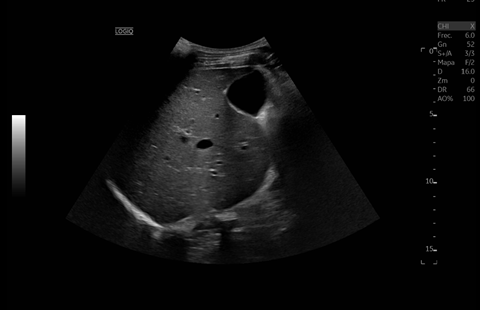

TA 163/83 mmHg, T 39,1 °C, FC 119 lpm, SatO₂ 94%. Abdomen globuloso con molestias en epigastrio y ligera esplenomegalia, sin signos de irritación peritoneal, RHA presentes, puño percusión negativa. Sin alteraciones neurológicas ni otros hallazgos relevantes.

Diagnostico diferencial: Fasciolasis Hepatica, hidatidosis hepatica, Etiología metastasica.

Juicio clínico: Síndrome febril agudo en contexto de infección hepatica probable por Fasciola Hepatica . Esplenomegalia y trombocitopenia.